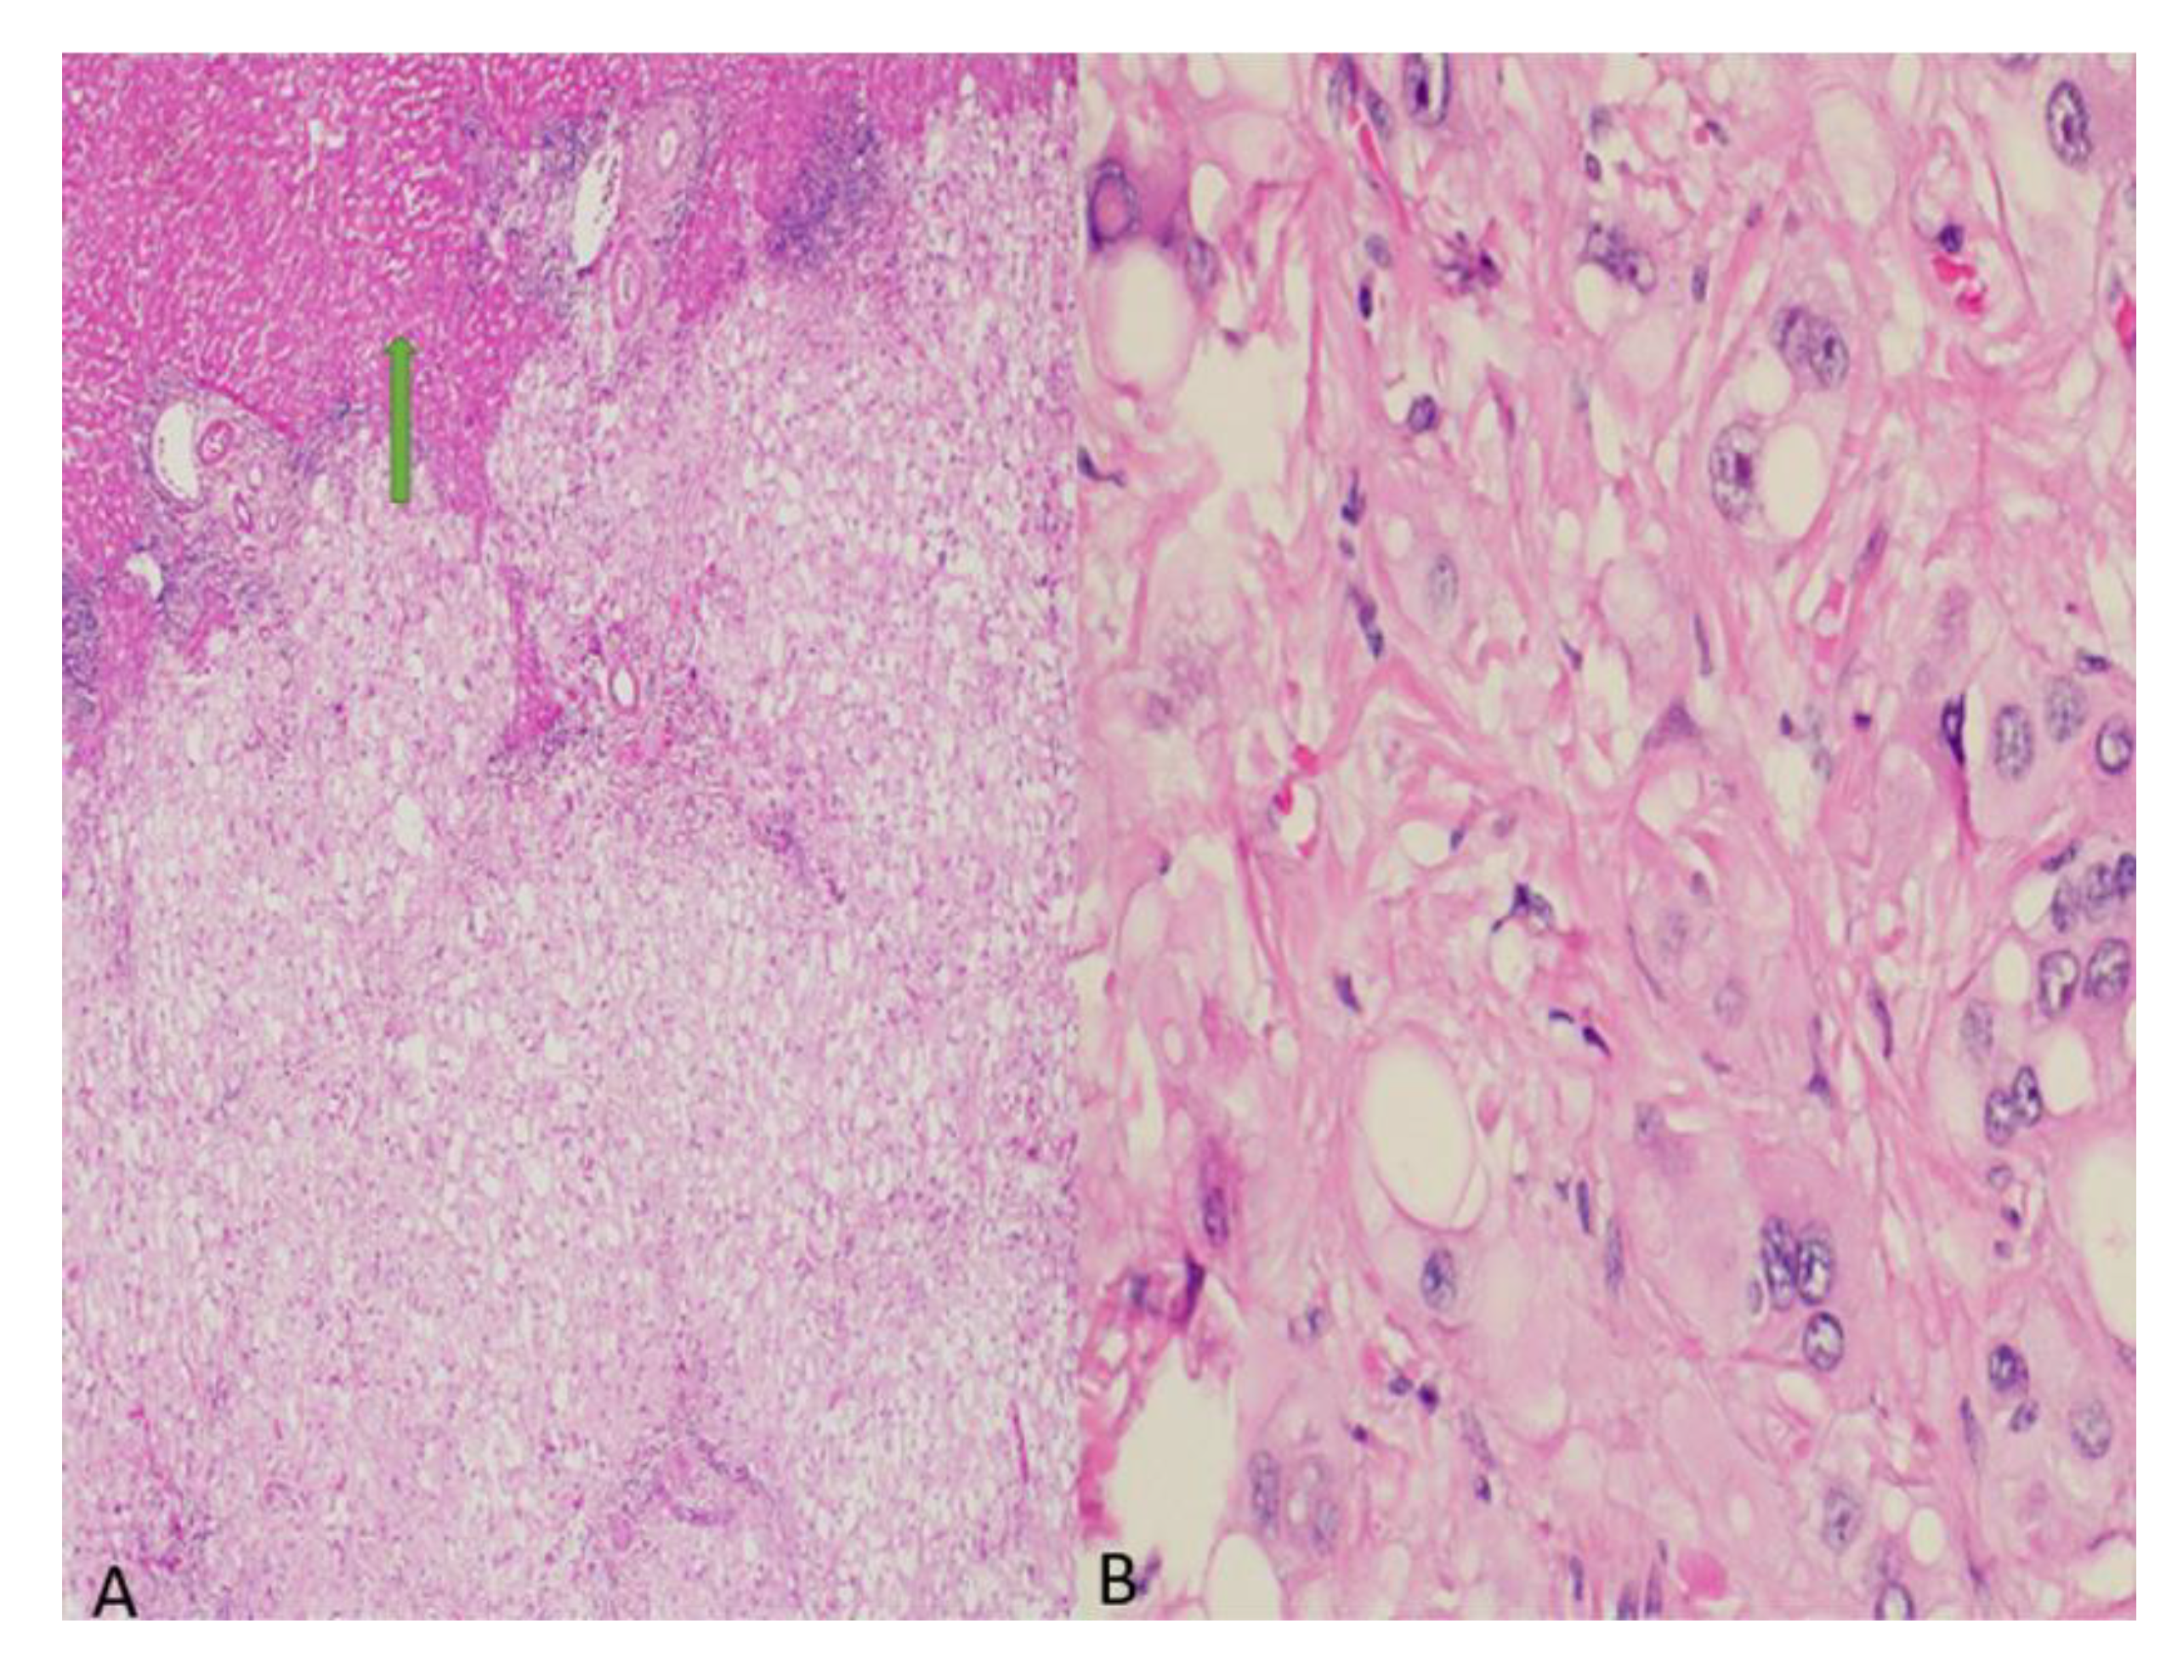

2. Case Presentation

3. Discussion